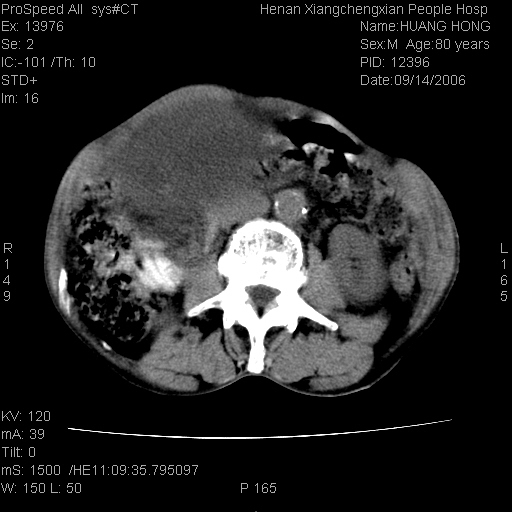

患者, 男, 80岁, 发现上腹部包块1年余,无其它不适.2006-9-14ct片是喝水后扫描2006-9-15ct片没喝水扫描![]() ![]() ![]() ![]() ![]() ![]() ![]() ![]() ![]() ![]() ![]() ![]() ![]() ![]() ![]() ![]() 以上是喝水片 以下是空腹片 ![]() ![]() ![]() ![]() ![]() ![]() ![]() ![]() ![]() ![]() ![]() ![]() ct:胰腺前方、肝脏与胃之间可见巨大类圆形囊性低密度影,大小约152mmx145mmx118mm,上缘平t11椎体上缘,下缘平l3椎体下缘,密度均匀,ct值15hu,其内呈多房分隔,囊壁薄且光滑,边界清晰,周围组织及器官明显受压。肝脏实质内未见异常密度影,胆囊未见异常,胰腺密度未见异常,脾脏大小、形态及密度未见异常,腹膜后间隙未见肿大淋巴结影。 印象:胰腺前方、肝脏与胃之间巨大类圆形囊性低密度影.性质待定。多考虑:.肠系膜巨大囊肿。 守望可可西里发言:支持楼主,考虑肠系膜囊肿,多为小肠系膜。 ysxyy发言:我总觉得这个病人虽然很像肠系膜囊肿,但还是应该强化一下; 下面这几幅图里肿块和主动脉的关系不太清,不知能否除外血管性来源? ![]() ![]() ![]() 病理结果:横结肠系膜间叶瘤.部分区域间质细胞增生活跃. 病理图片 ![]() 良性间叶瘤:是指由两种或两种以上的间叶组织所构成的混合性肿瘤.肿瘤仅发生在腹膜后和肠系膜,.前者较后者多发.良性间叶瘤常发生在肾或四肢,腹膜后较少见,各年龄均可发病.女多与男,预后较好,但术后易复法. 恶性间叶瘤:由两种以上恶性间叶组织成分组成. 光镜:肿瘤由脂肪/血管/平滑肌构成. 原贴地址: http://www.radinet.com.cn/forum_view.asp?forum_id=4&view_id=16217 ok |